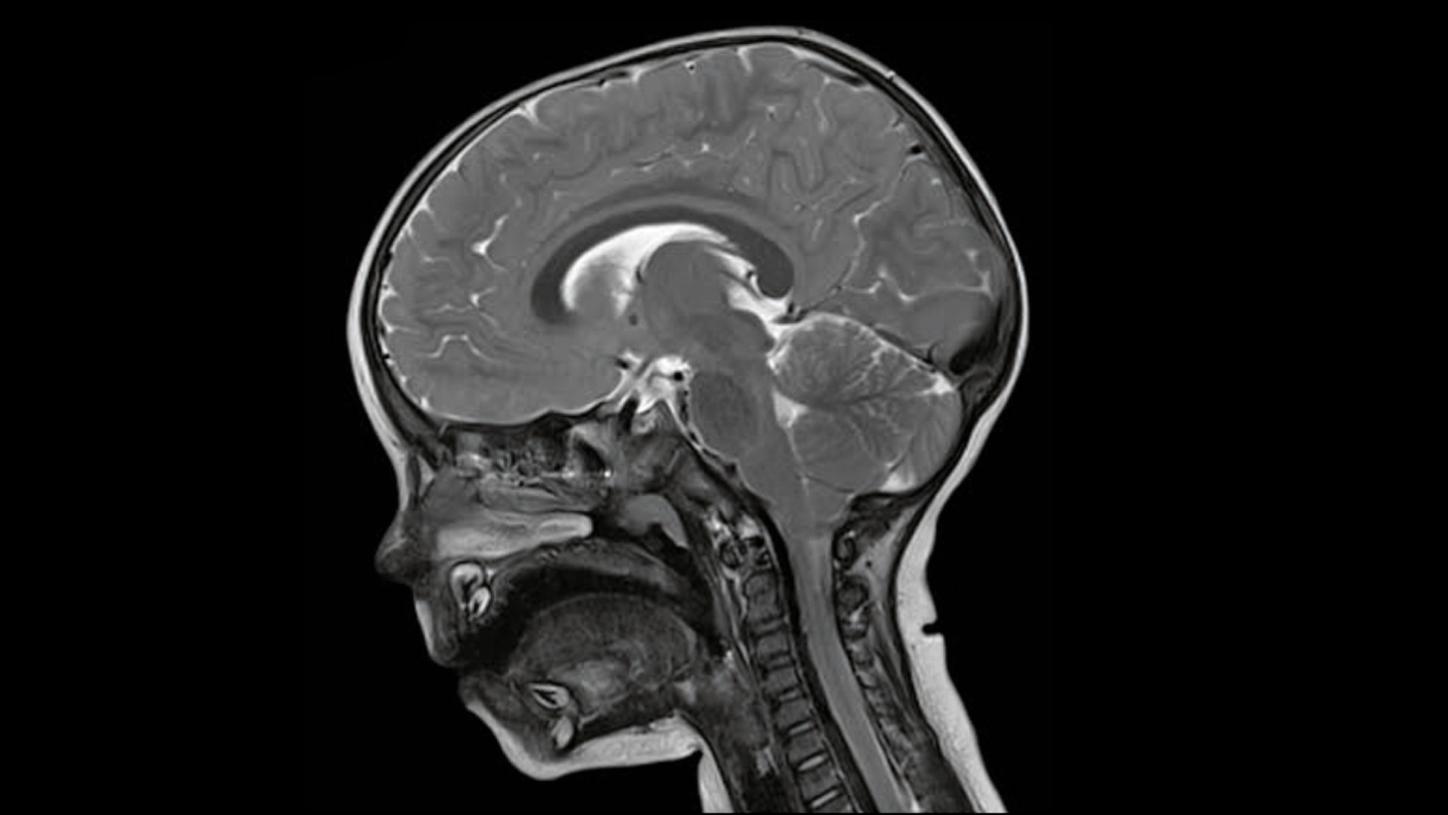

The influence of the medical image in healthcare is constantly growing. Diseases are detected earlier and treatments become more effective. When its usage is expanded beyond the field of diagnostics, entering the arenas of prevention and therapy, it can significantly contribute to lowering costs in healthcare on a global scale.